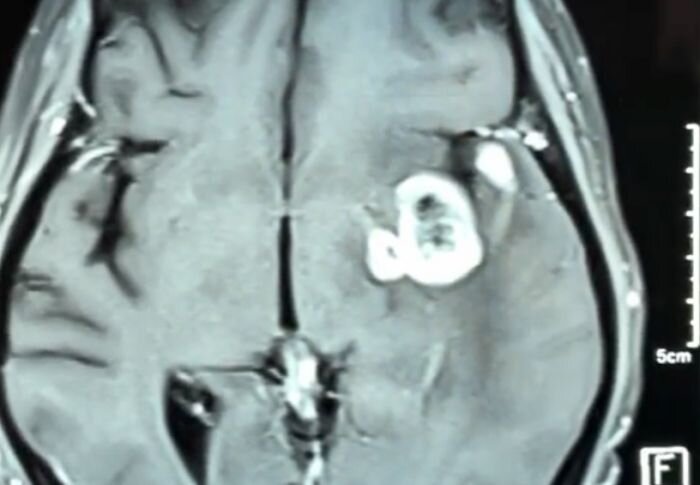

Cerebral ependymomas

Brain gliomas